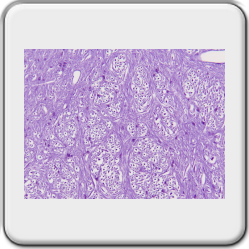

Nissle substance in motor neurons, cresyl violet acetate staining

The large nucleus has a prominent nucleolus[2] and finely divided chromatin. Also found are many free polyribosomes and a highly developed RER (rough endoplasmic reticulum[2]). All this indicates high protein synthesizing activity for structural and export proteins (neurotransmitters[2]). As early as the nineteenth century, RER and free polysomes[2], by staining with cresyl violet (Nissl staining), could be observed as basophilic elements in the cytoplasm: the Nissl substance. The amount of this substance varies according to the type of nerve cell and its activity. There is a lot of Nissl substance in large nerve cells, such as motor neurons[2].

Preparation details,

The brain stem and cerebellum were taken from a Guinea pig and fixed in formaldehyde 4%.

The block was embedded in paraplast plus and then cut on an A&O 820 rotary microtome. Thickness is 4µm.

To obtain a large-format image that is quite "zoomable" afterwards, the author took 171 shots with a Leitz plan Fluotar 16x objective. Used a Moticam 2300 camera on a Leitz Orthoplan microscope.

Click on the image to the right and zoom in on various structures of the brainstem and cerebellum.